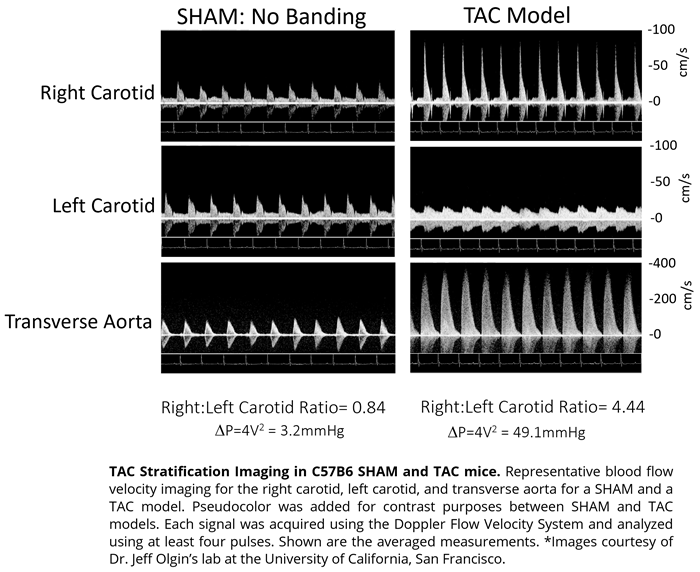

Pressure-overload (Stenosis)

Area

TAC Banding Model

Flow parameter

- Carotid peak velocity ratio (R/L)

- Estimating the pressure gradient across stenosis using stenotic jet velocity

Imaging gallery - Doppler Flow Velocity System

Mouse - TAC Procedure Imaging. Image Credit: Scintica Instrumentation Inc.